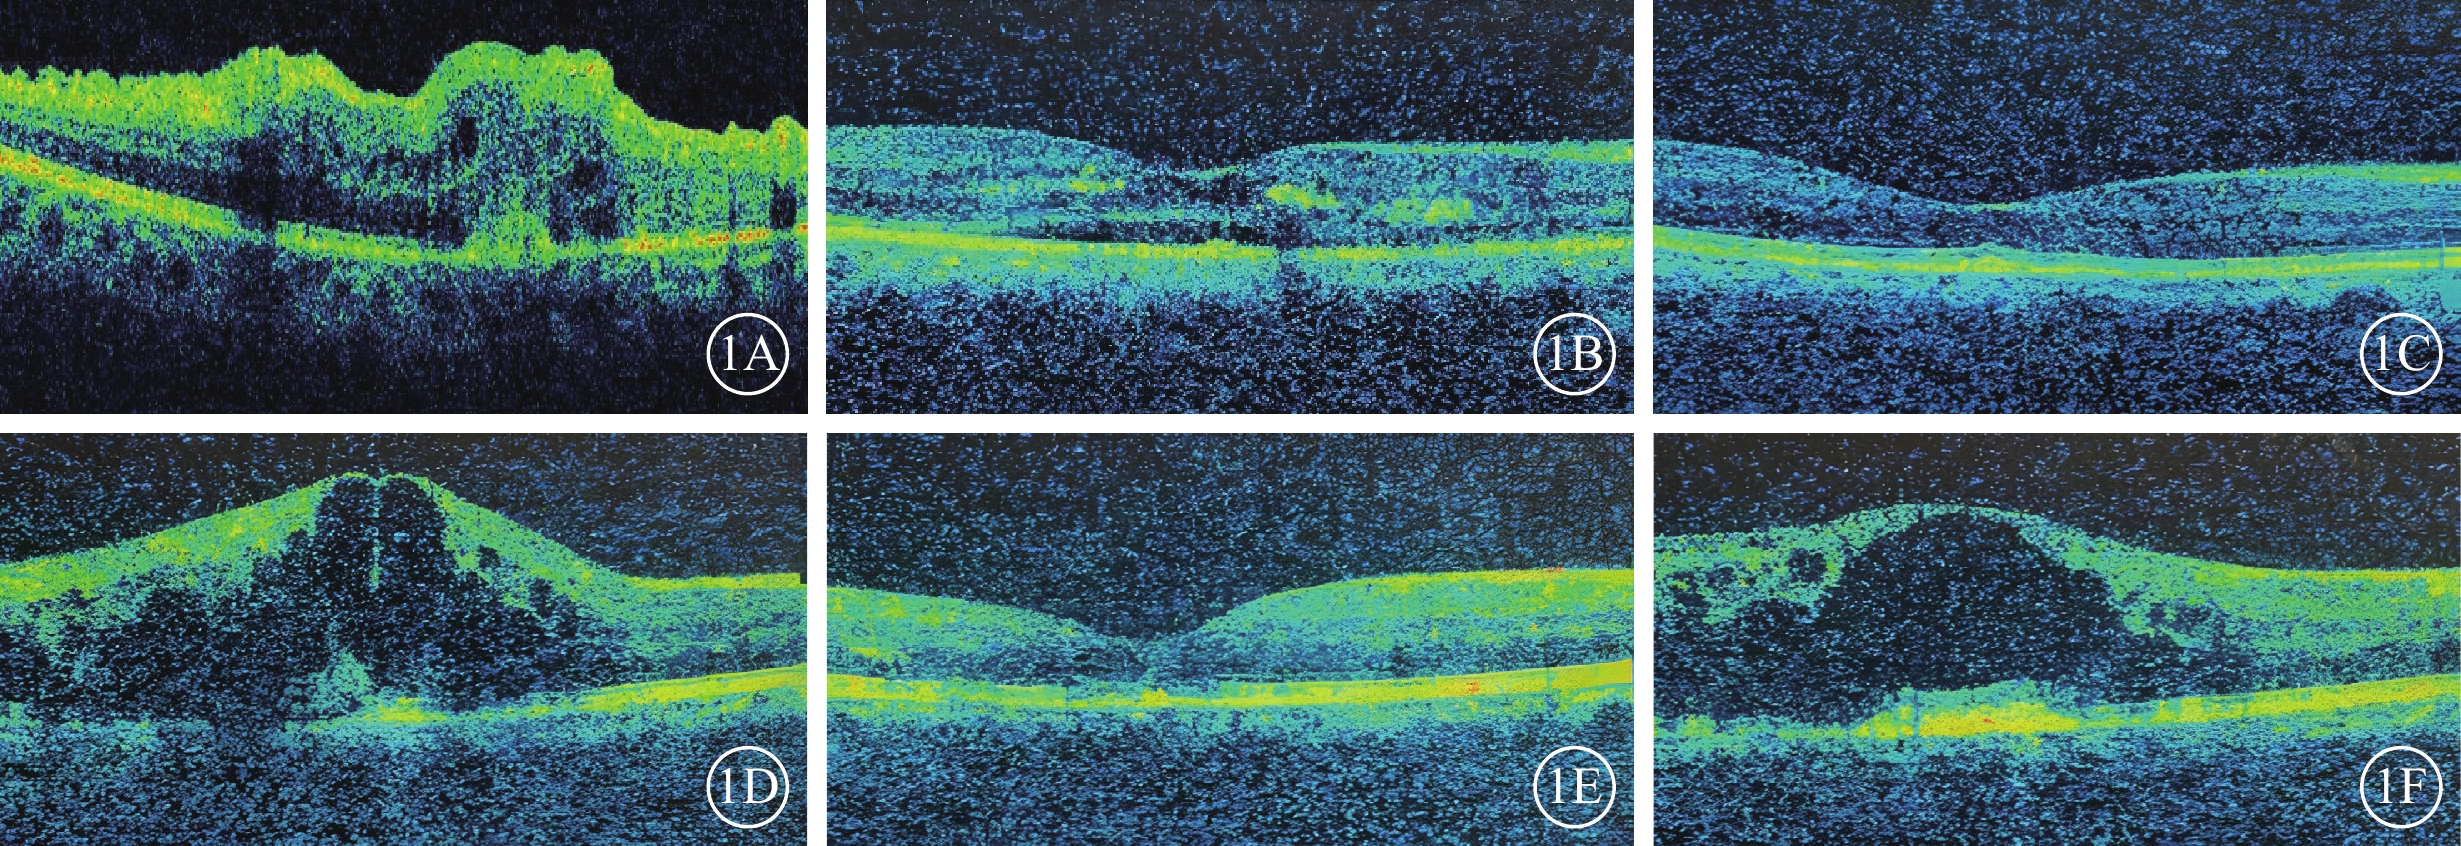

治療后每一個月隨訪1次,連續6個月。隨訪時采用治療前相同設備和方法行相關檢查。根據治療后6個月時logMAR BCVA與治療前logMAR BCVA差值,將訓練集98例患者98只眼分為預后良好組(差值≤-0.3)、預后不良組(差值>-0.3)(圖1),分別為58例58只眼、40例40只眼。